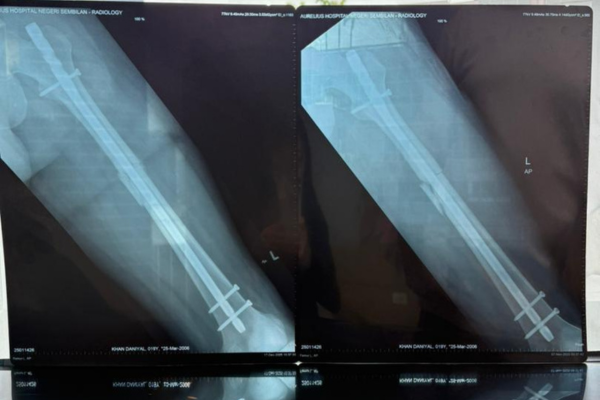

Femur Fracture (Post Surgery)

Fractures of the femur are relatively common injuries and are not typically amenable to nonoperative treatment. Early surgical fixation is recommended, for instance an Intramedullary nailing surgery.

Femoral Fracture Fixation Surgery: Intramedullary Nail (Cite from: Medical Legal Art)